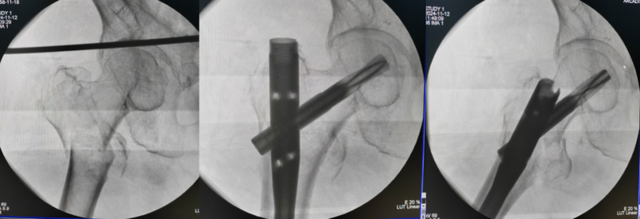

股骨粗隆间伴粗隆下骨折PFNA髓内钉内固定